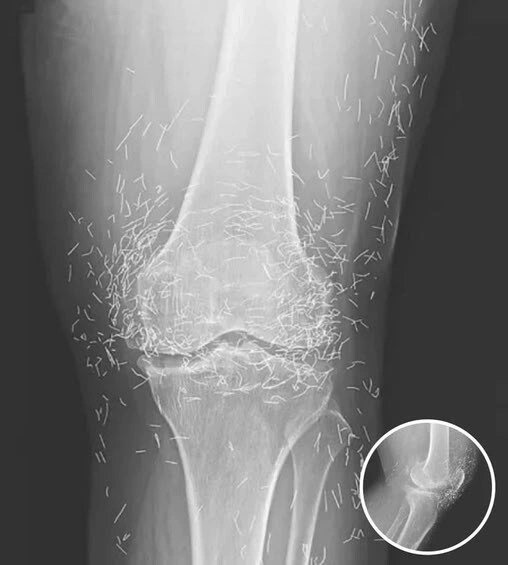

What began as a routine medical examination quickly turned into a startling discovery that left doctors both surprised and concerned. A 65-year-old woman in South Korea, who had been struggling for years with persistent knee pain, underwent a standard X-ray scan. What physicians saw on the screen was anything but ordinary — hundreds of tiny gold needles embedded deep within her knee tissue.

Knee X-ray showing multiple small metallic needle fragments embedded in tissue

Doctors were stunned to discover hundreds of tiny gold needles scattered within the patient’s knee tissue during a routine X-ray.